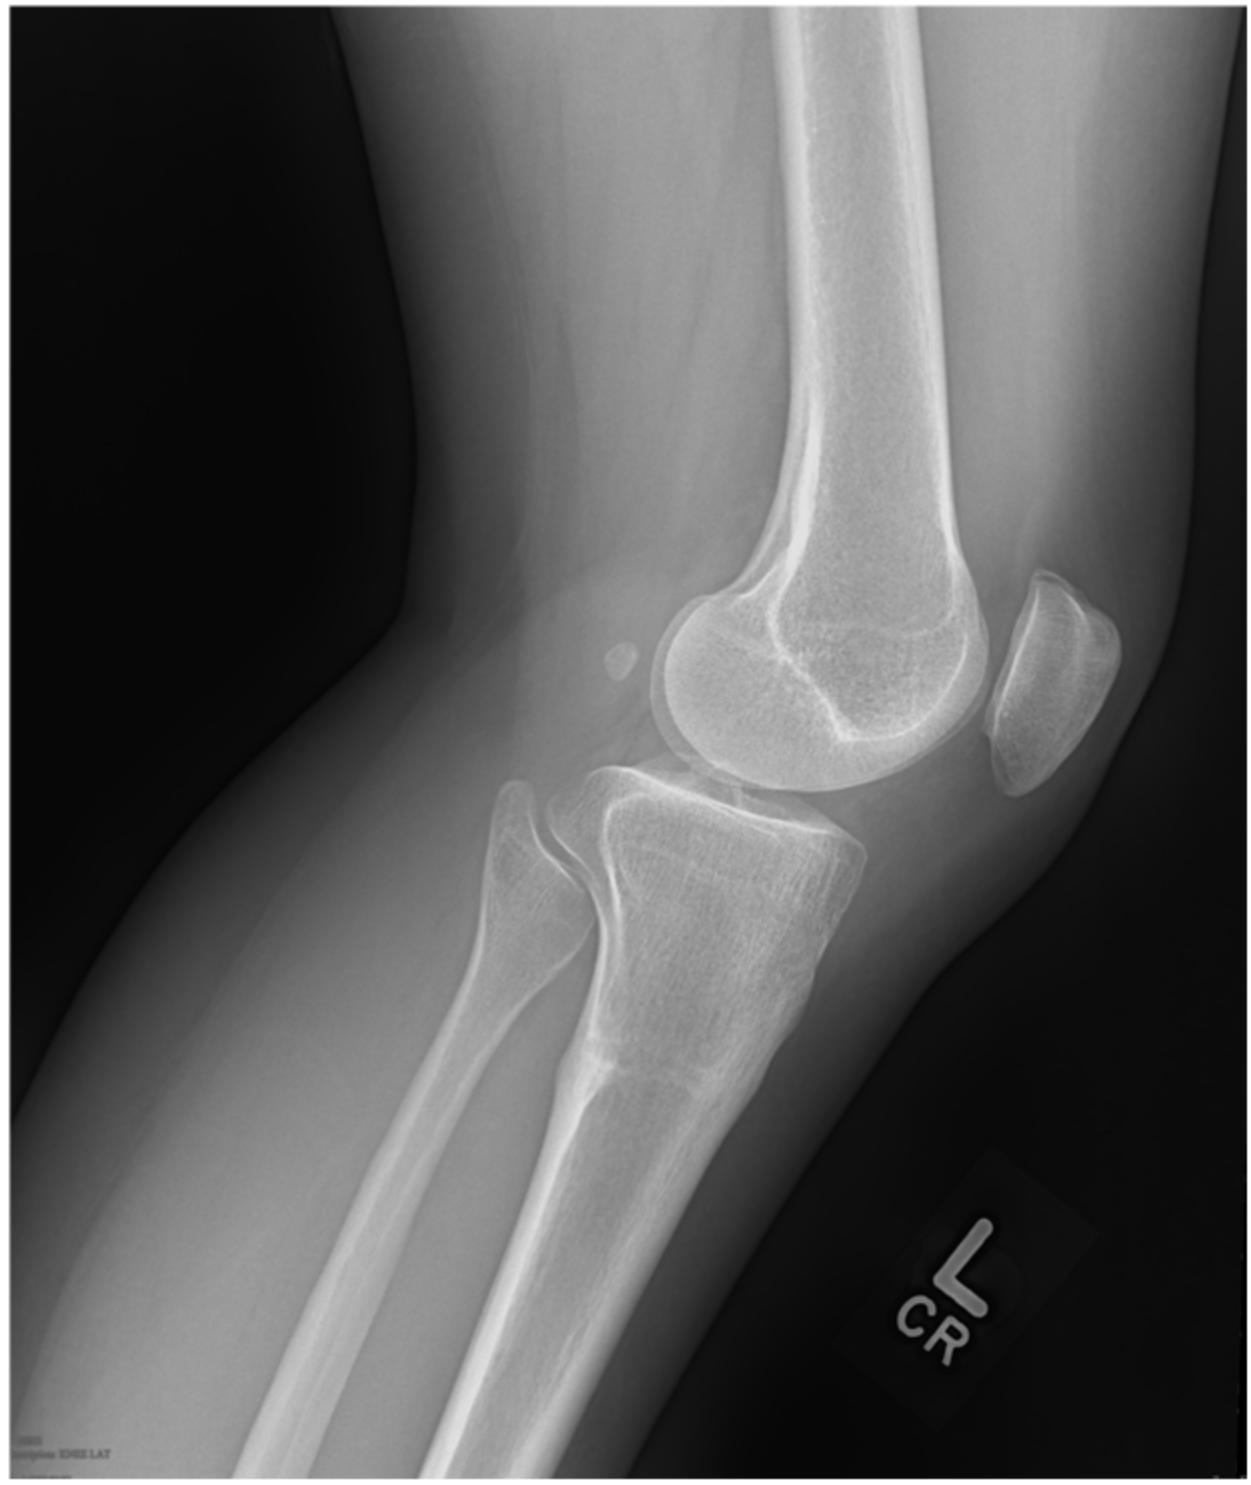

2. Case 1